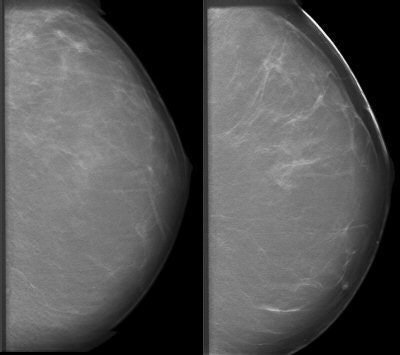

![]() |

| Patient who had previously undergone breast-reduction surgery. On left, surgical scars can be seen at the top half of DBT image. At right, tissue structures, which would have been partially obscured by the scar tissue, are visible. Images courtesy of Dexela and Mark B. Williams, Ph.D., University of Virginia, Charlottesville. |